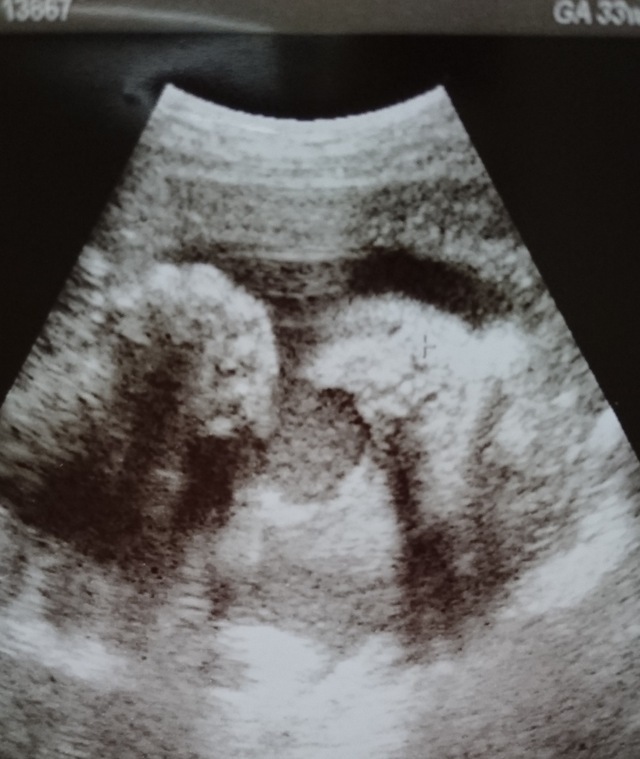

33週0日(33w0d・男の子)|riiiii さん(24歳)

エコー写真撮影時のエピソード:

お腹が大きくなってきてよく動いていました。 仕事をギリギリまでしていたけど、周りの音をきいてよくお腹の中でボコボコけったり背伸びをしたりしてる感じがあり、お腹の中は狭かったかなぁ?!

先生には、順調に大きくなってますね!!って言われました。エコーの時には顔の前に手を動かし、とってもかわいらしかったです。